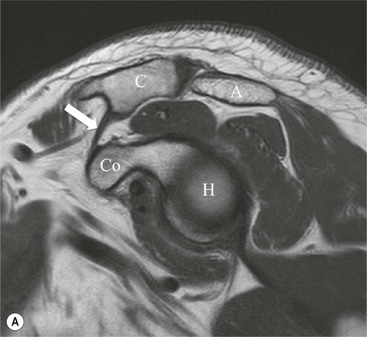

The long head of biceps (LHB) tendon arises from the supraglenoid tubercle and superior labrum. The intra-articular component passes between the subscapularis and supraspinatus tendons in a region known as the rotator interval, and enters the bicipital groove on the anterior aspect of the humeral head. The LHB is stabilised within the rotator interval by the biceps pulley comprised of coracohumeral and superior glenohumeral ligaments.

Tears of the LHB pulley and subscapularis tendon may lead to medial subluxation of the LHB tendon from the bicipital groove. The LHB may also show features on tendinopathy or may eventually rupture.